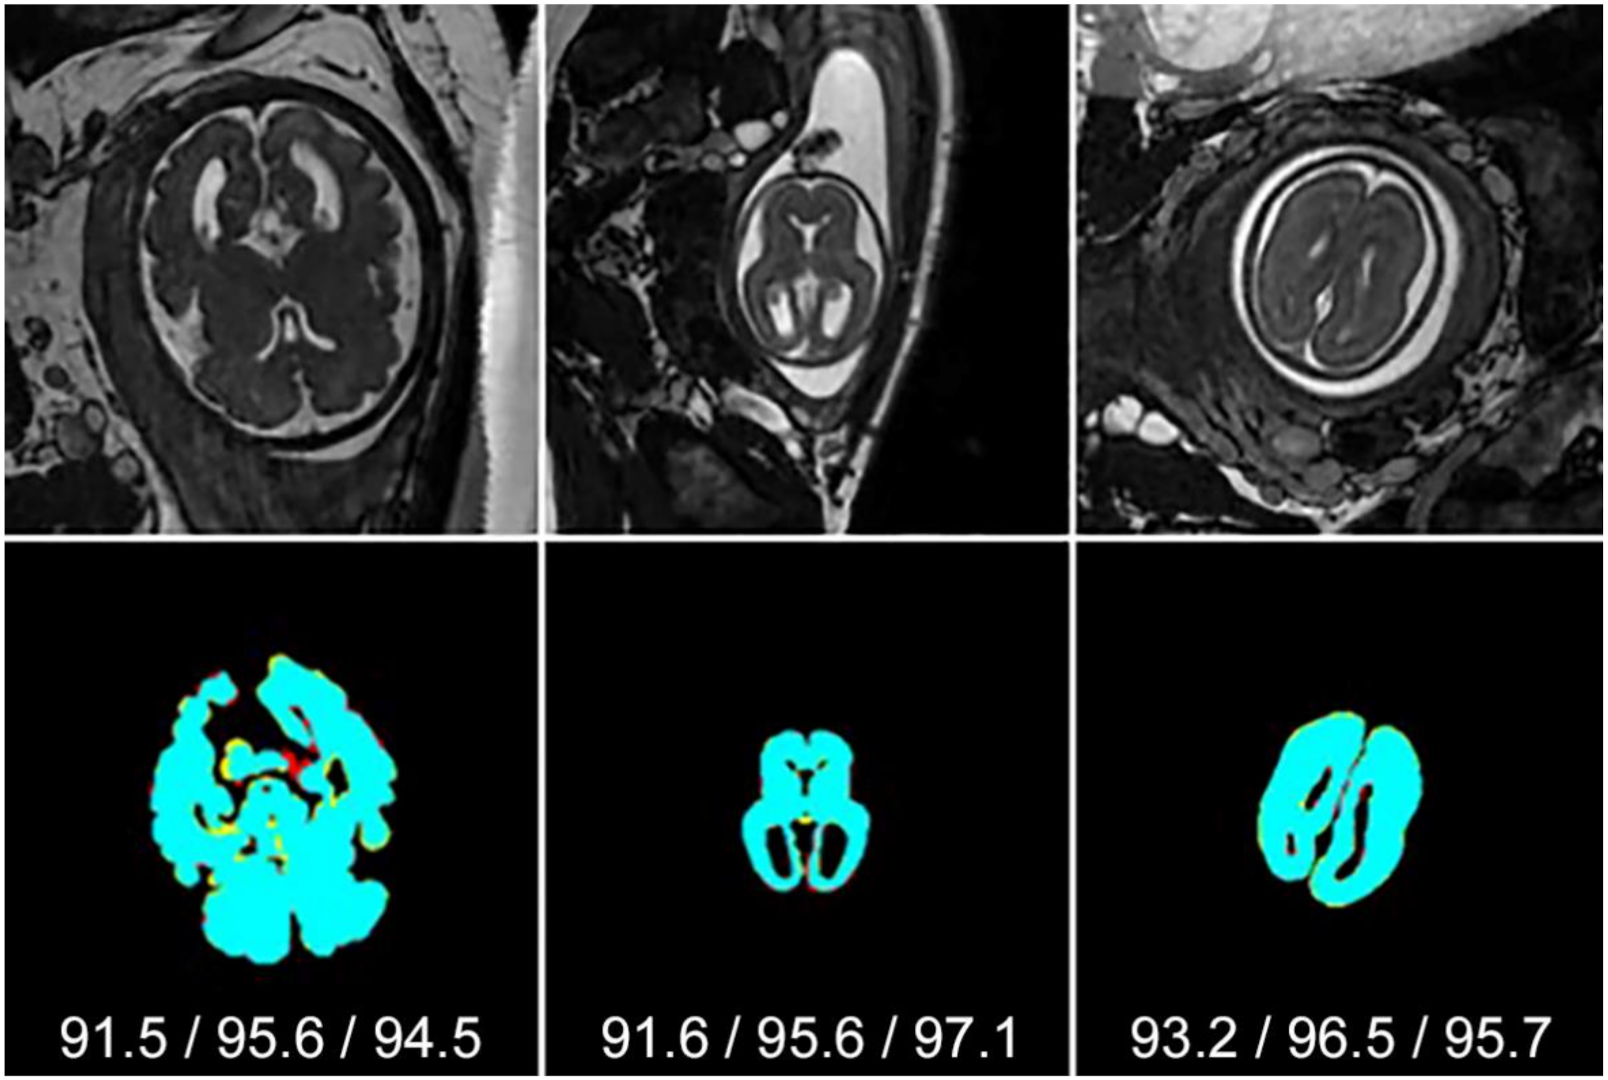

4.4. Visual Comparison with Other Network Architectures

4.5. Segmentation of Challenging Cases